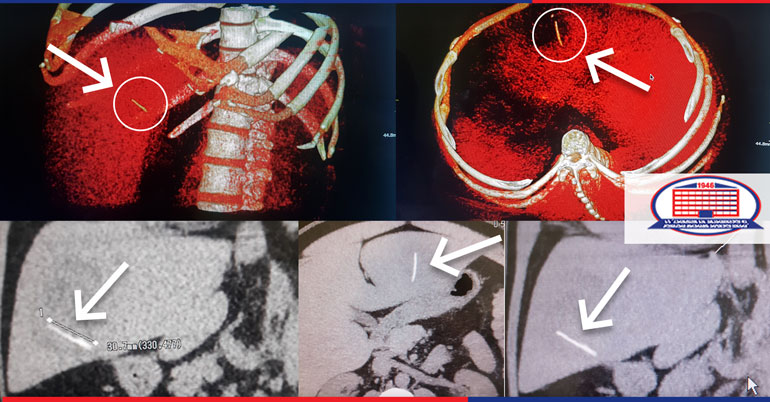

печень Хирургия